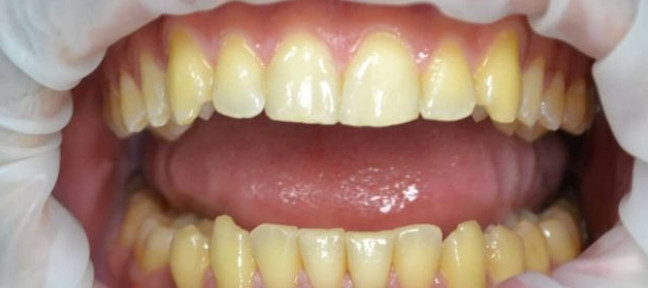

Чистка зубов Air-flow

Чистка зубов ультразвуком с полировкой. Доктор очень бережно отнесся к сгустку крови образовавшемуся на травмированном камнем участке десны. Это даст возможность максимально быстро восстановиться сосочку десны. Наложенная в дальнейшем лекарственная повязка ускорит процесс.

Доктор: Фалилеев Алексей Константинович